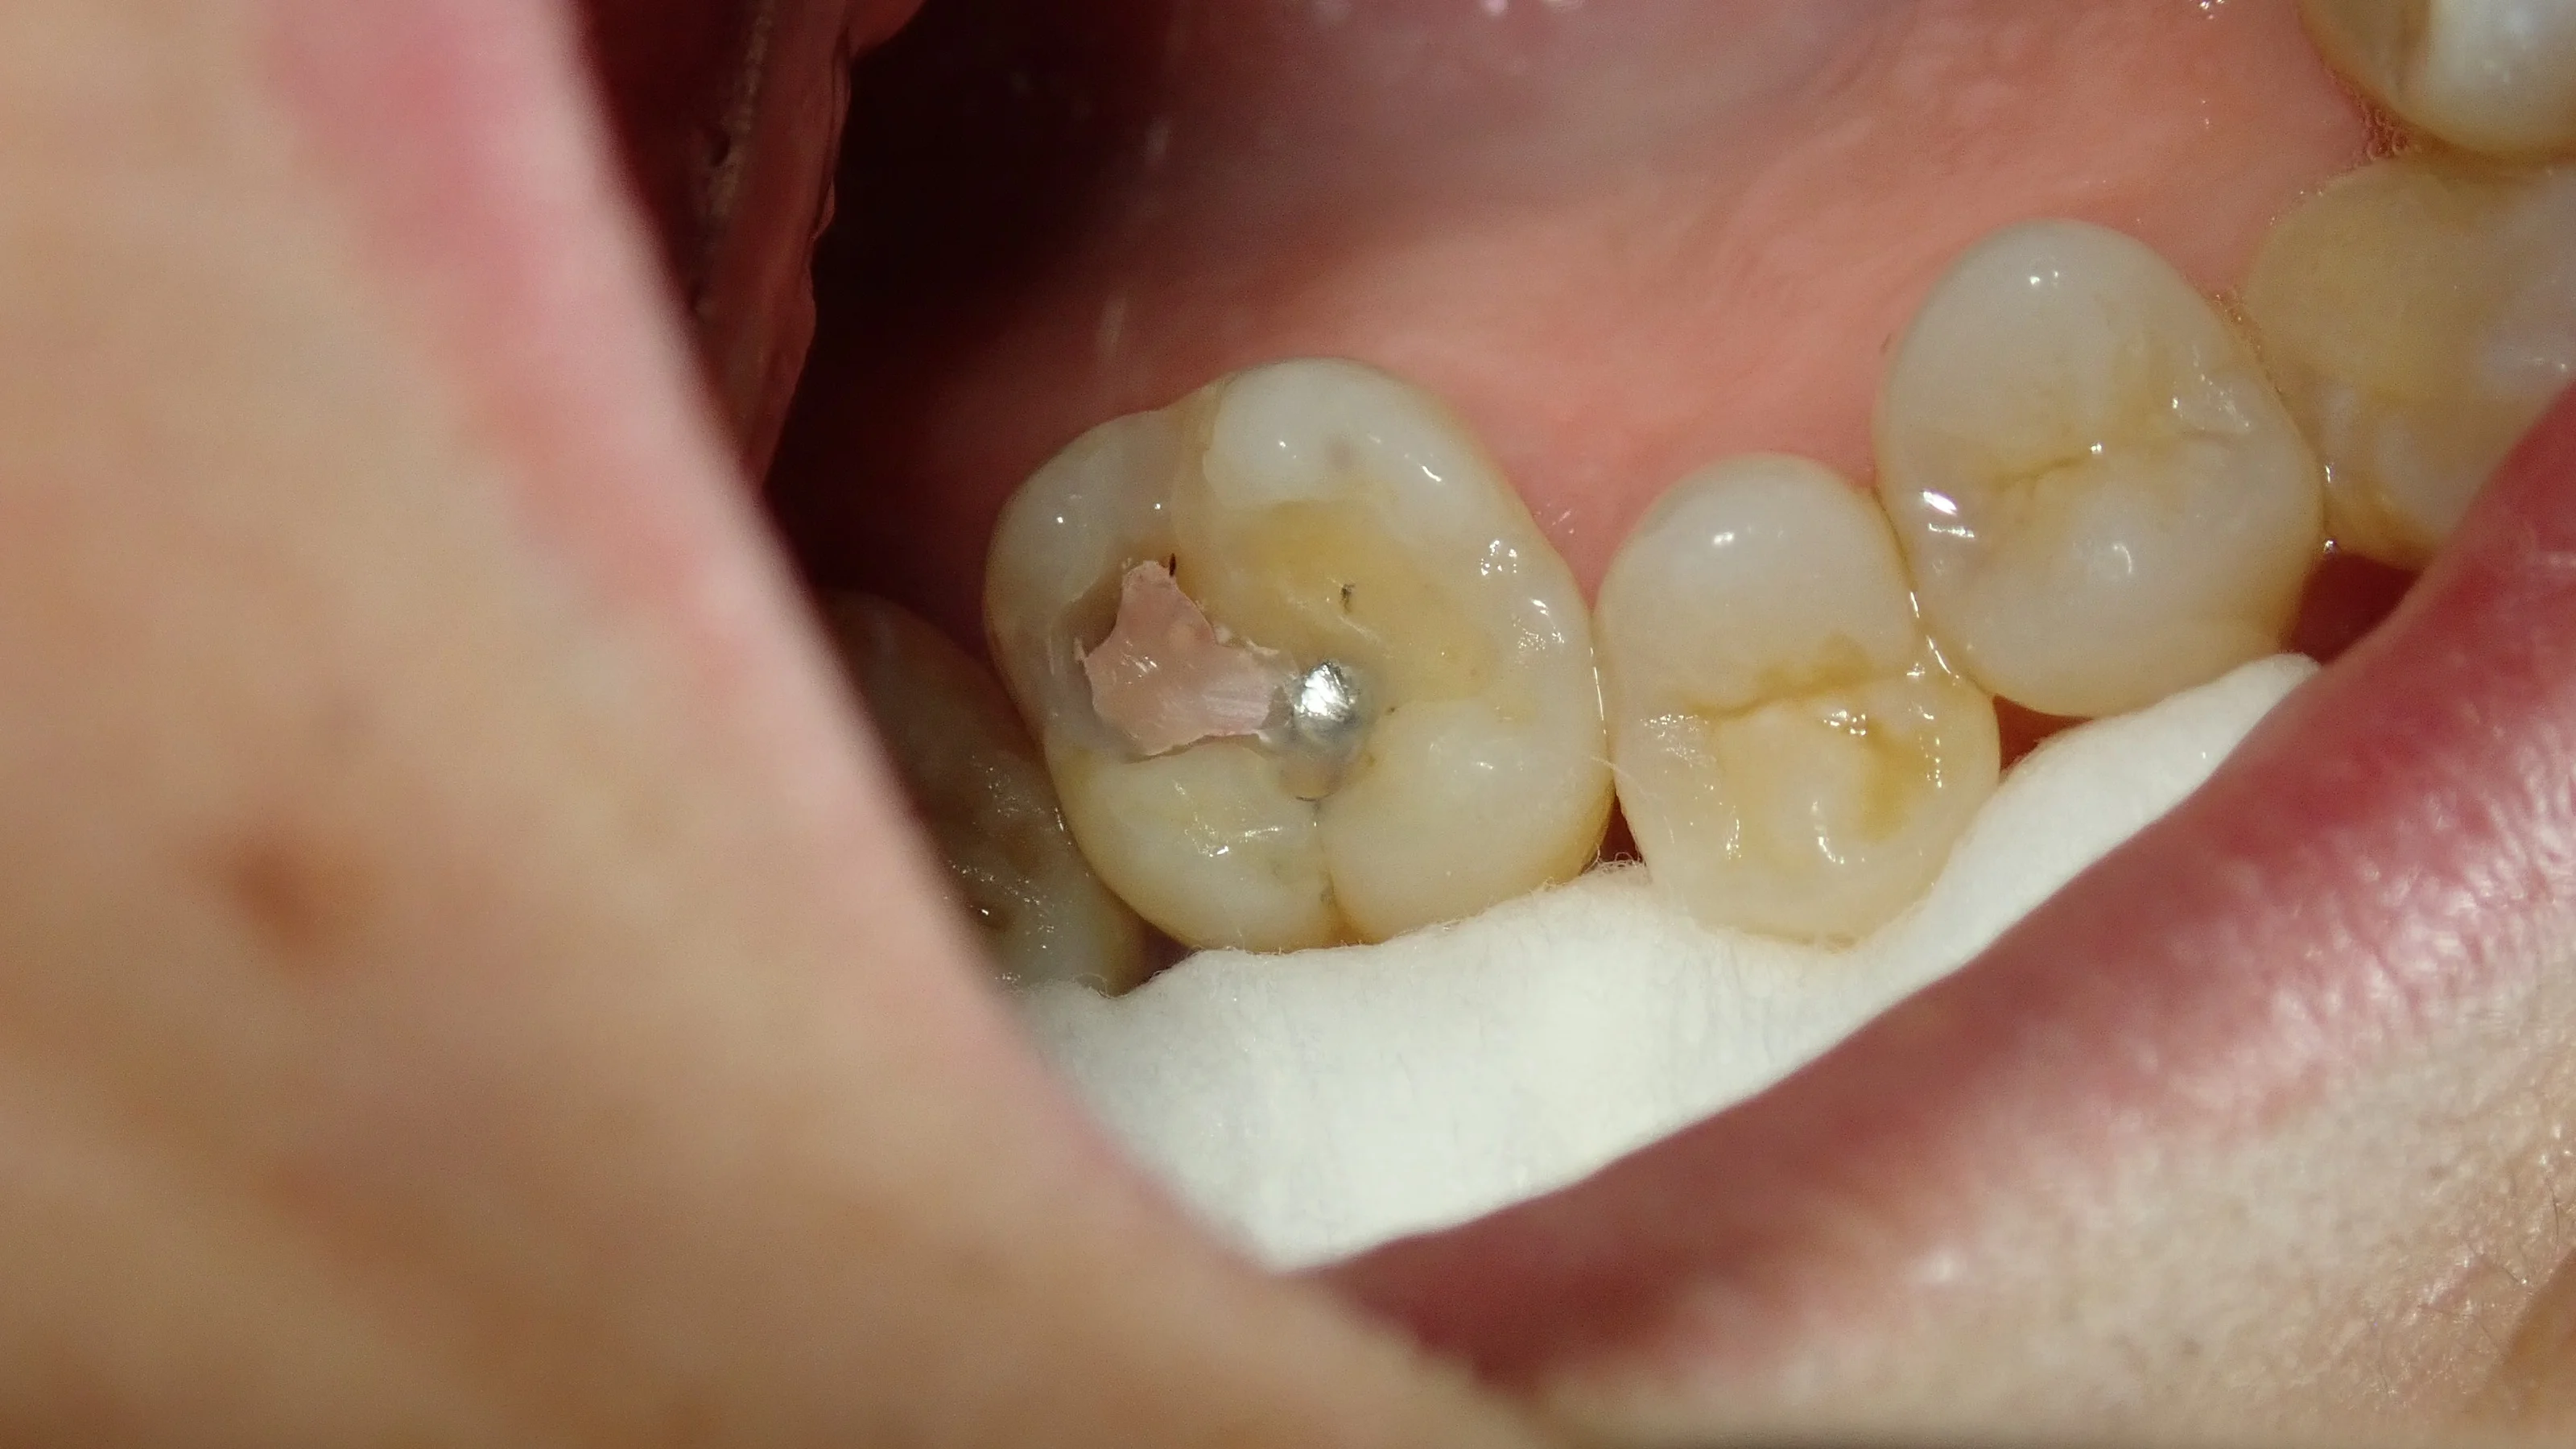

ではいつも通り、術前からです。

画面の左から2番目の歯ですね。

保険内でコンポジットレジンが詰められています。

裂溝部(歯に存在する溝の部分)の再現は全くされていないのっぺらぼうな詰め物になっていますが、保険で行う治療は審美や持ちは度外視で、「虫歯を取って咬めれば良い」という感じですので、こういう凹凸の全くないコンポジットレジンは正直よく見ます。

そしてレジンを除去していくと・・・

レジンとは別の材料が2つ出てきました。

ピンク色の方が恐らくはグラスアイオノマーセメントと呼ばれるもので、黒い方が元々詰められていた金属でしょうね。

レジンには「神経に対する為害作用が存在する」と言われていた時代があり、その時代の治療ではよく見かけるものです。(確か平成1桁台とか聞いた記憶があります。)